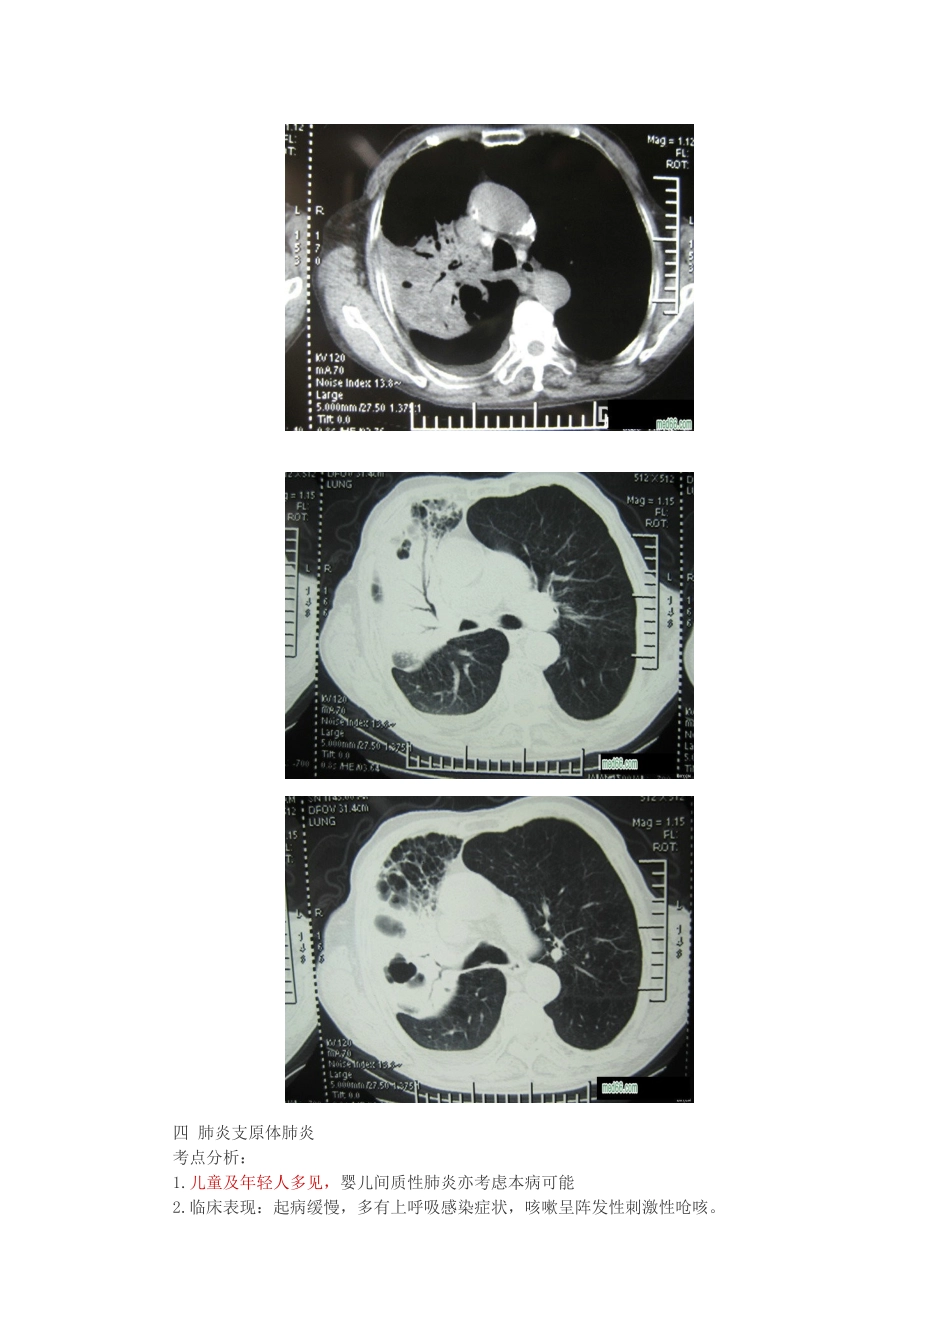

2025 年临床执业医师呼吸内科复习要点-肺部专题及测试1. 肺炎定义:终末气道、肺泡和肺间质的炎症。2.分类:目前应用最多的分类①社区获得性肺炎(CAP):是在医院外罹患的感染性肺实质炎症,包括具有明确埋伏期的病原体感染而在入院后平均埋伏期内发病的肺炎② 医院获得性肺炎(HAP)是患者入院时不存在、也不在埋伏期,而于入院 48 小时后在医院内发生的肺炎。一 肺炎链球菌肺炎1.病因:肺炎链球菌为革兰染色阳性球菌,有荚膜,不产生毒素,不引起坏死或形成空洞,其致病力是由于多糖荚膜对组织的侵袭作用。2.典型表现:①发病前有明显诱因病史,②发热、胸痛、咯铁锈色痰。③查体时急性肺实变体征:可以应用诊断学上的视触叩听。辅助检查:血象升高超显,C-反应蛋白升高,痰培育可明确病原体,胸部 X 线示:多表现大片浸润阴影或实变影。3.治疗:提醒:肺炎链球菌肺炎停药指标:热退 3-5 天,总疗程不少于 5 天。注意:肺炎链球菌肺炎在发病机制上说不引起坏死或空洞,但胸部 X 线在消散期中炎症浸润逐渐吸收,可有片状区域吸收较快,呈现“假空洞”,多数病例在起病 3-4 周后才完全吸收。2. 二 葡萄球菌肺炎考点分析:1.病因:葡萄球菌为革兰染色阳性球菌,致病物质主要是毒素和酶,病理上属于化脓性炎症(而肺炎链球菌病理上属于急性纤维素性炎症)。2.临床表现:起病急,寒战高热、咳嗽咳痰,痰呈粉红色乳状痰及全身中毒症状明显。体征:多数是肺实变体征医`学教育`网整理3.辅助检查:血象升高超显。胸部 X 线示:肺段或肺实变,可形成空洞,单个或多发液气囊腔是其特征之一,X 线阴影易变性是特征之二。一般 X 线表现为肺浸润、肺脓肿、肺液气囊肿及脓气胸等多种表现。4.治疗:提醒:金黄色葡萄球菌肺炎(MRSA)首选万古霉素。三 肺炎克雷白杆菌肺炎考点分析:1.多见于老年人、营养不良、COPD 及全身衰竭患者2.临床表现:起病急,高热、咳嗽、咳痰和胸痛,痰呈砖红色胶冻状痰。3.辅助检查:血象升高,胸部 X 线示:多见右肺上叶,双肺下叶,典型表现是叶间裂下垂。4.治疗:三代头孢四 肺炎支原体肺炎考点分析:1.儿童及年轻人多见,婴儿间质性肺炎亦考虑本病可能2.临床表现:起病缓慢,多有上呼吸感染症状,咳嗽呈阵发性刺激性呛咳。3.胸部可无阳性体征4.辅助检查:血象可正常或升高,冷凝集试验阳性,起病 2 周后测定可阳性,若滴度效价≥1:32,尤其是当滴度逐步升高时,具有诊断价值。支原体 lgM 抗体阳性。...